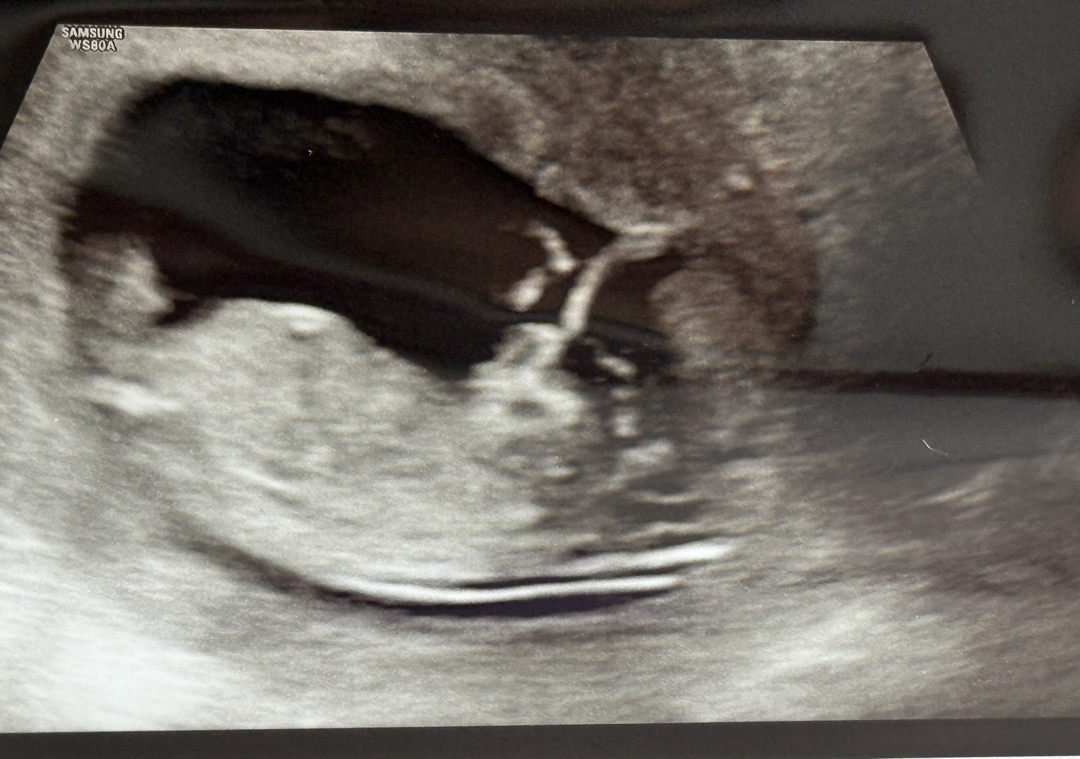

애기가 많이 움직여서 잘 보이진 않눈데ㅜ 각도법 고수님들 부탁드려요

딸 같아요.